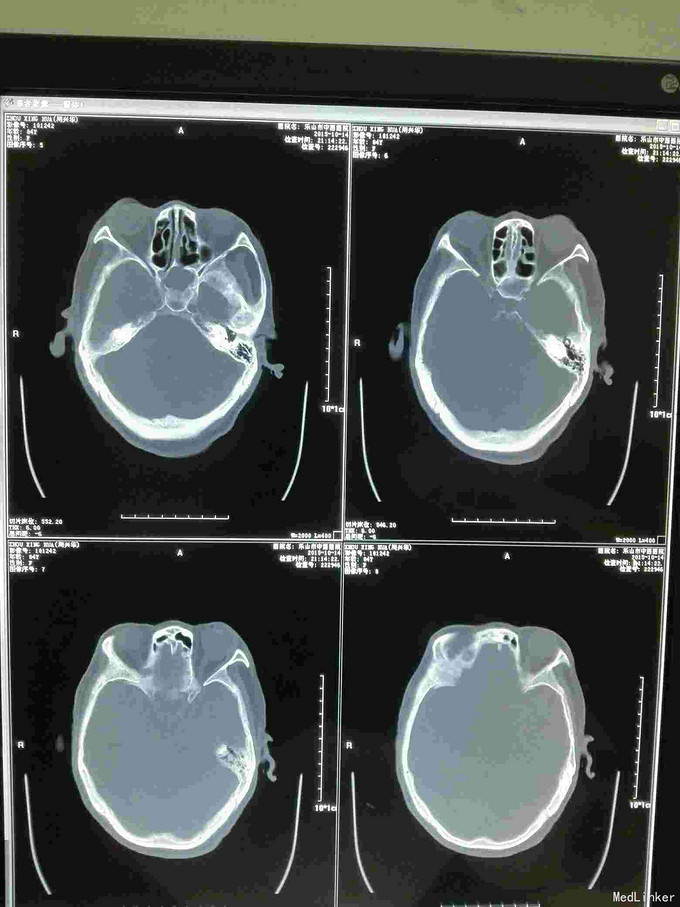

急诊CT病例

昏迷不醒就诊